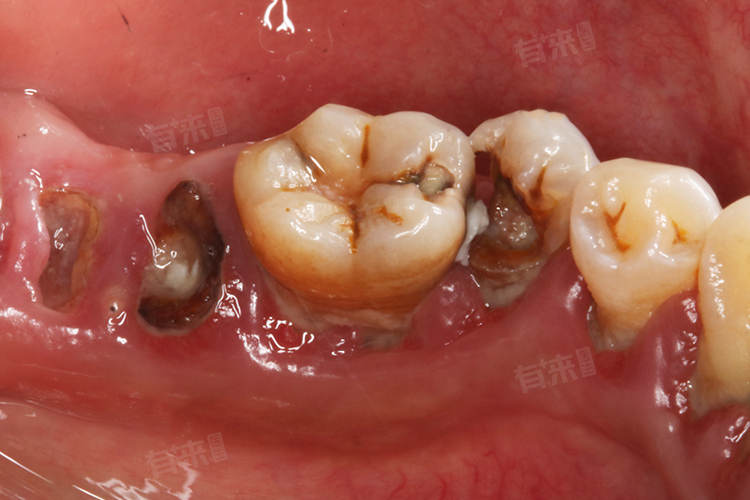

3、细菌侵袭:细菌是引发烂牙的关键因素,口腔内存在着大量的细菌,其中变形链球菌、乳酸杆菌等产酸菌与龋齿的发生密切相关。这些细菌会附着在牙齿表面,形成牙菌斑。牙菌斑中的细菌利用食物中的糖类进行代谢,产生酸性物质,如乳酸等。这些酸性物质会使牙齿硬组织中的矿物质溶解,导致牙齿脱矿,进而破坏牙齿的结构,形成龋洞的初期病变。

4、牙齿结构缺陷:牙齿的窝沟较深且狭窄,在发育过程中矿化程度不足,食物残渣容易滞留其中,不易被清洁,为细菌滋生提供理想的场所。釉质发育不全的牙齿,其表面的釉质结构薄弱,抗酸性差,在面对口腔内细菌产生的酸性物质时,更容易发生脱矿和龋坏。

- 龋齿充填修复:若烂牙处于龋齿阶段,应及时进行充填修复。医生会先去除龋坏组织,然后根据龋洞大小与位置选择合适的充填材料,如树脂材料,其颜色与牙齿相近,美观且坚固耐用。